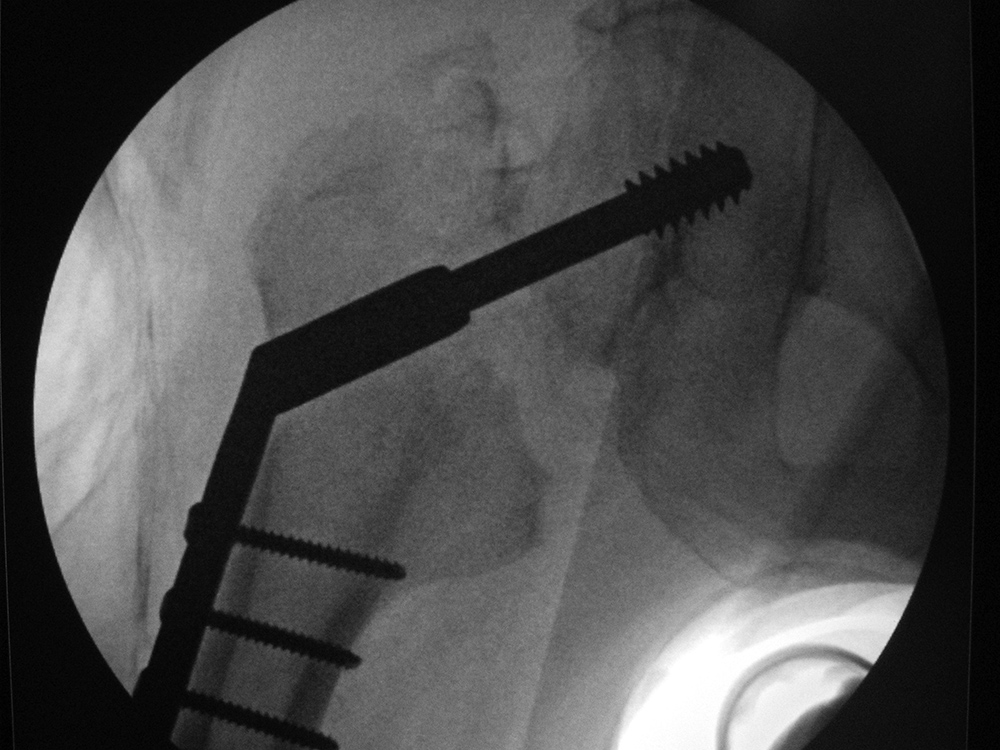

Intraoperative fixation of an intertrochanteric fracture demonstrates a cephalomedullary device with the tip of the cephalic screw positioned too short and very inferior in the neck (very large tip-apex distance). |

Subsequent fracture fixation failure observed as the head and neck segment of the femur flexed 90 degrees with cut-out of the screw approaching the hip joint. |